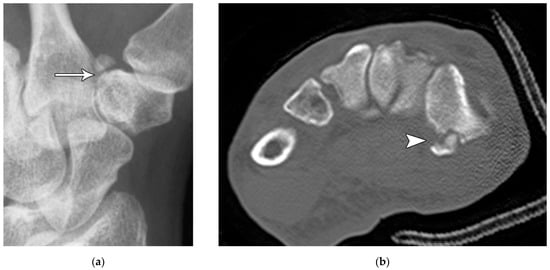

Figure 12. (a) Medial oblique hand radiograph showing a well-corticated ossicle in the expected location of the trapezial tubercle, a rare anatomic variant known as os trapezium secundarium. These may represent chronic fracture fragment nonunion. (b) Axial reformatted CT in a different patient showing a trapezium ridge fracture (arrowhead).

Trapezium fractures are divided into body and ridge fractures. Body fractures are often associated with fractures of the base of the first metacarpal [11]. These are further subdivided into vertical intra-articular, dorsal, radial tuberosity, ulnar tuberosity, comminuted, and horizontal fractures (Figure 11). Ridge fractures either involve the base or the tip. Ridge base fractures are a result of direct palmar trauma. These can appear similar to the rare trapezium secundarium (Figure 12a), which is an accessory ossicle that is found adjacent to the trapezial tubercle. The trapezium ridge fractures that involve the tip (Figure 12b) are avulsions caused by a sudden tension force applied to the transverse carpal ligament/flexor retinaculum. Management of nondisplaced fractures involves immobilization for 4 to 6 weeks for proper healing. If displaced, trapezial ridge fractures are at risk for nonunion due to pull from the transverse carpal ligament. Surgical fixation or fragment excision are options, particularly in high-performance athletes [17]. Trapezial body fractures that are displaced greater than 2 mm and/or have carpometacarpal subluxation require surgical fixation to prevent long-term osteoarthrosis.